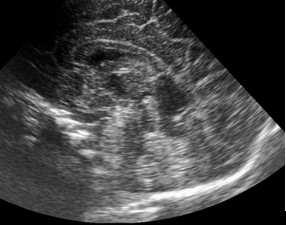

Nace recién nacido de 34 semanas de edad gestacional (EG) con un peso adecuado. A las 31 semanas de EG se observa en la ultrasonografía prenatal una disgenesia de cuerpo calloso asociada a pies equinovaros bilaterales, se realiza RM fetal que confirma la disgenesia con escaso desarrollo de la parte posterior y descarta otras anomalías a nivel intracraneal, el estudio Array-CHG fue normal y se descartaron infecciones en liquido amniótico. El estudio genético mostró un cariotipo 46 XY. El parto fue eutócico. La prueba de Apgar: 9/10/10. pH arteria umbilical: 7,27. No requirió reanimación. En la USC postnatal, se aprecia ( Figuras 1A y 1B).

La sección coronal y parasagital media de la USC muestran un cavum velum interporsitum (CVI) de gran tamaño que en la época fetal dificultó visualizar la parte más posterior del CC (esplenio). La asociación de disgenesia de CC y la deformidad extrínseca (pies equinovaros) que presentaba nuestro paciente dio pié a realizar un estudio genético prenatal por la posible asociación con un síndrome polimalformativo.

Figura 1A US. Corte coronal